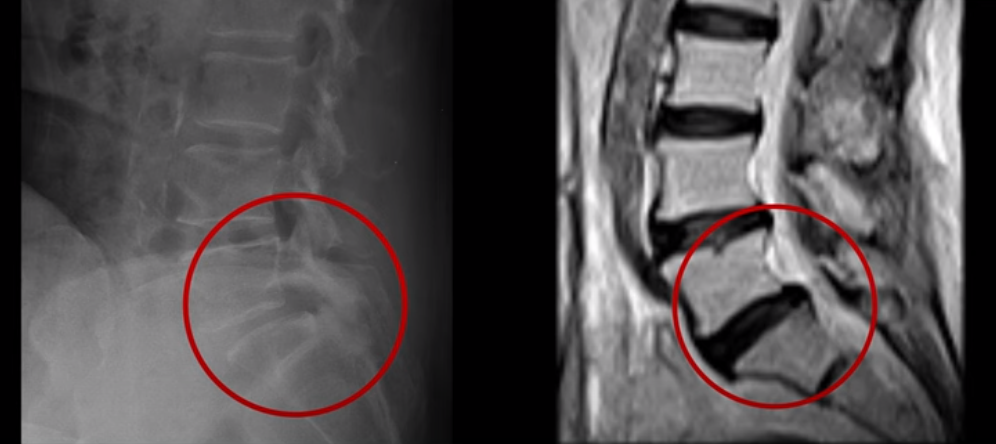

우선 이 환자분의 X-ray를 보면 5번 1번에 전방전위증으로 인한 불안정성이 있습니다. 척추가 불안정하므로 전방전위로 뼈가 밀려 나간 정도가 MRI에 보이는 것보다 X-ray 굴곡상태에서 보는 게 훨씬 더 심해 보입니다. 또 척추 여러 마디에 퇴행성 병변이 보입니다.

먼저 5번 1번에 척추관 내의 황색인대의 골화 현상이 보이고

후관절의 퇴행도 심해 보입니다.